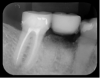

Fig 15. Radiograph showing radiopacity of material.

Figure 15